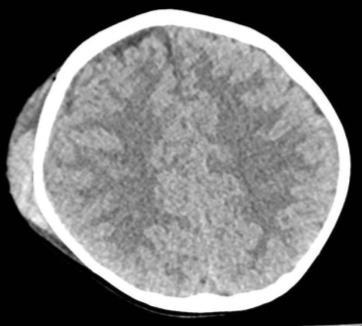

CT Scan of the Brain, Facial Mass, and Spine:

- Multiple fractures of the skull base and cranial vault;

- No vertebral fractures (no spinal cord compression);

- Displaced fracture of the mandibular condyle and right orbital floor;

- Ventriculoperitoneal shunt (VPS);